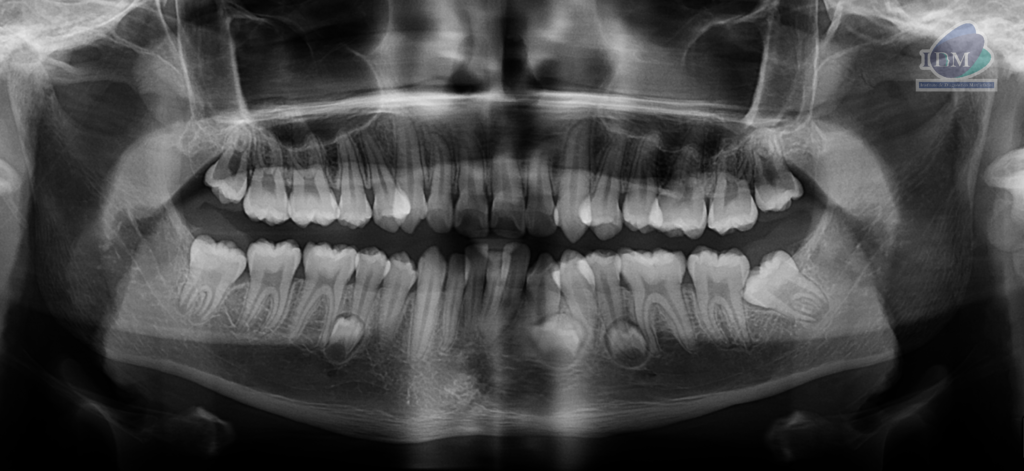

Radiografia Panorámica

A la evaluación de la radiografía panorámica se evidencia tres folículos supernumerarios en cuerpo mandibular de ambos lados.